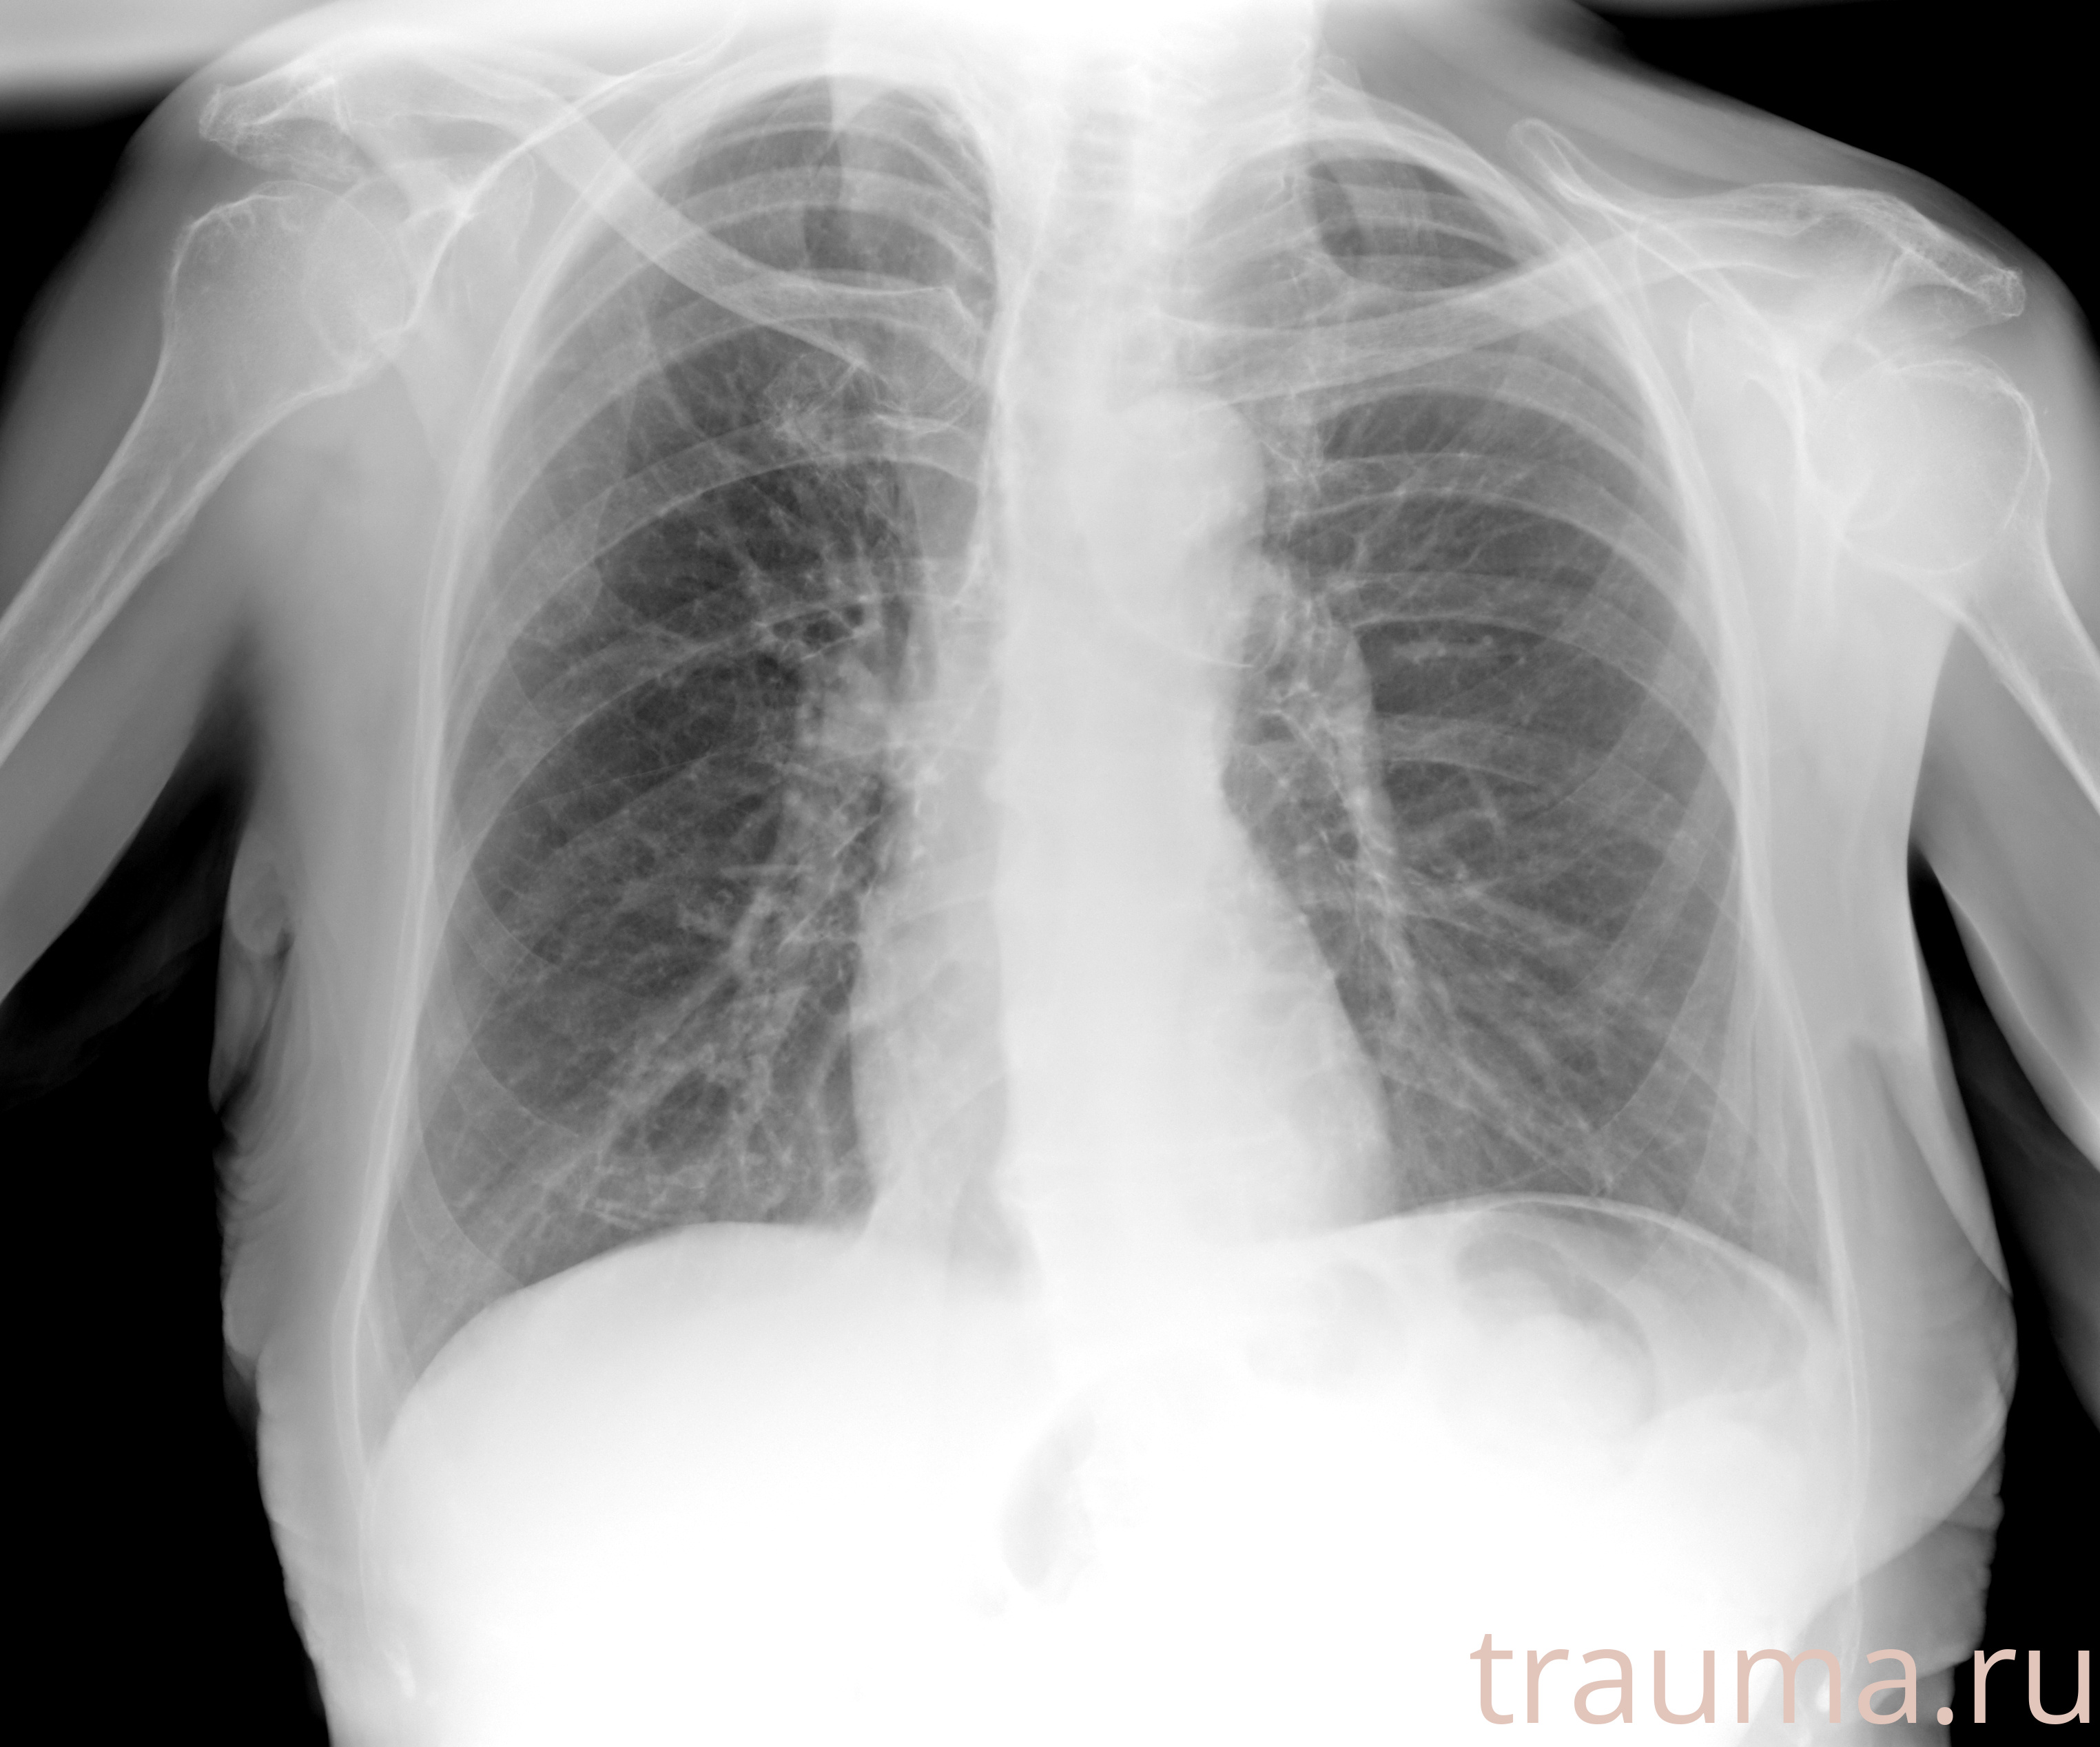

Рентгенограммы

Рентген на дому: по вашему адресу приезжает врач-рентгенолог, травматолог-ортопед с мобильным рентгеновским аппаратом, проводит диагностику травмы или заболевания, делает необходимые рентгенограммы, дает рекомендации по дальнейшему лечению. Получить качественные снимки в домашних условиях возможно благодаря уникальной методике, разработанной МосРентген Центром для института  Склифосовского